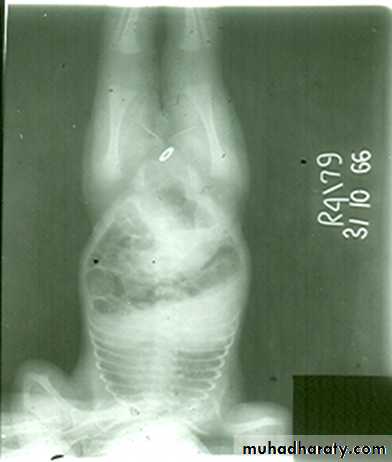

• 1- Anal Atresia ( imperforated Anus).2-Meconium ileus ( neonatal obstruction).3-Duplication.4-Malrotation .5-Mega colon ( Hirschsprung’s disease ,aganglionic colon ).Imperforated anus

• Clinically the newborn delivered with abdominal distension and failure to pass meconium .• The anomaly vary from thin mucosal membrane to severe developmental anomalies of rectum and according to that there are two types :-

• A- Low type ( perineal approach ).

• B- High type (Abdominal approach ).

• The value of radiological examination to assess these types prior to surgery .

• Technique of Examination :• 1- The examination should be done at least 12-18 hours after delivery to allow time for swallowed air to reach the rectum .

• 2- The anal dimple is identified by metallic marker

• 3- AP and Lateral views are taken with inverted position(invertogram) .

• Signs of low atresia :

• 1- Multiple air fluid level due to obstruction .

• 2- In AP view the distance between the terminal rectal segment and the marker should not exceed 2 cm.

• 3- In lateral view the terminal air shadow is seen above the pubo-coccygeal line.

• Signs of high atresia

• 1- In AP view the distance more than 2 cm .• 2-In lateral view the terminal air is below the pubo-coccygeal line .

Low type

High type